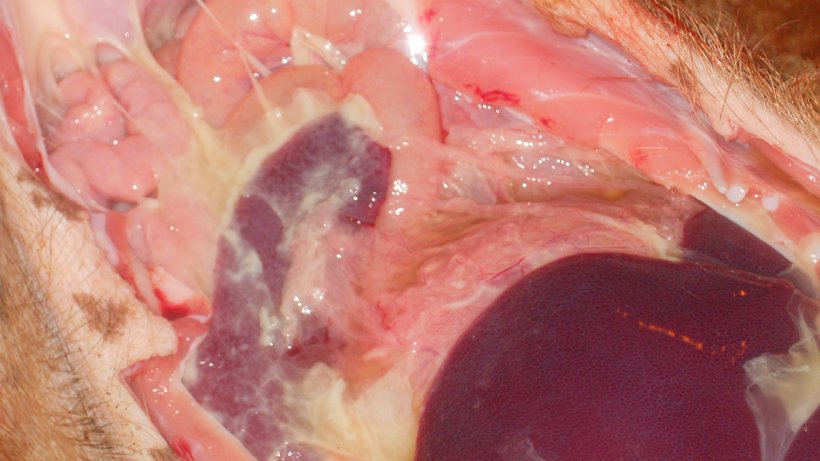

Dans cette étude, les auteurs ont évalué un modèle d'infection par Mhr en utilisant du matériel infectieux associé à des cellules dans les mêmes portées à sept, dix, treize et seize semaines. Le protocole expérimental d'infection à Mhr utilise des porcelets obtenus par césarienne et privés de colostrum, en obtenant une péricardite et une boiterie sévère. Les porcelets dans chaque groupe d'âge ont été inoculés avec Mhr sur 3 jours consécutifs: une injection intrapéritonéale de 20 ml au jour 0, une injection intraveineuse de 10 ml au jour 1 et une application intranasale de 10 ml (5 ml / fosse nasale) le jour 2. Il y avait aussi des animaux témoins de chaque groupe d'âge. Les porcs ont été observés quotidiennement du premier jour et jusqu'à 21 jours après l'inoculation au cas où ils présenteraient une boiterie. Ils ont été pesés avant la première inoculation et le jour 21, juste avant l'euthanasie. Après l'euthanasie, un examen macroscopique pathologique a été effectué à la recherche de signes de polysérite. Deux écouvillons ont été prélevés sur chaque porc, un sur le péricarde et un sur les surfaces articulaires des deux coudes et des deux genoux. Chez les animaux présentant une pleurésie ou une péritonite manifeste, des écouvillons de plèvre et de séreuse ont également été prélevés.

- La péricardite a été considérablement réduite de 87% à sept semaines à 4% à seize.

Les résultats de cette étude montrent que les porcelets étaient sensibles aux boiteries associées au Mhr au moins jusqu'à l'âge de seize semaines, alors que la polysérite associée au Mhr avait un pic à l'âge de sept semaines. Les pertes économiques causées par Mhr peuvent être attribuées à une réduction des performances (GMQ et conversion) et au fait que certains animaux doivent être abattus.